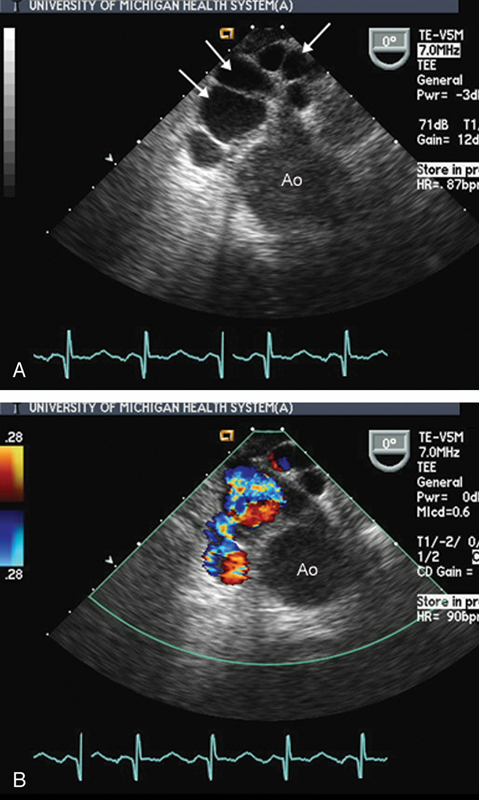

فحوصات تشخيصية لبعض امراض القلب والشرايين التاجية